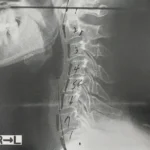

重度の頚椎ヘルニアの症例

重度の頚椎ヘルニア・肩から指までの痛みと痺れの症例 【大阪市 70代男性】 30年間接骨院に通院していましたが、頭痛と肩こりに加え腕の痛みと痺れが取れず、最近は腕も細くなってきたので整形外科へ。MRI…